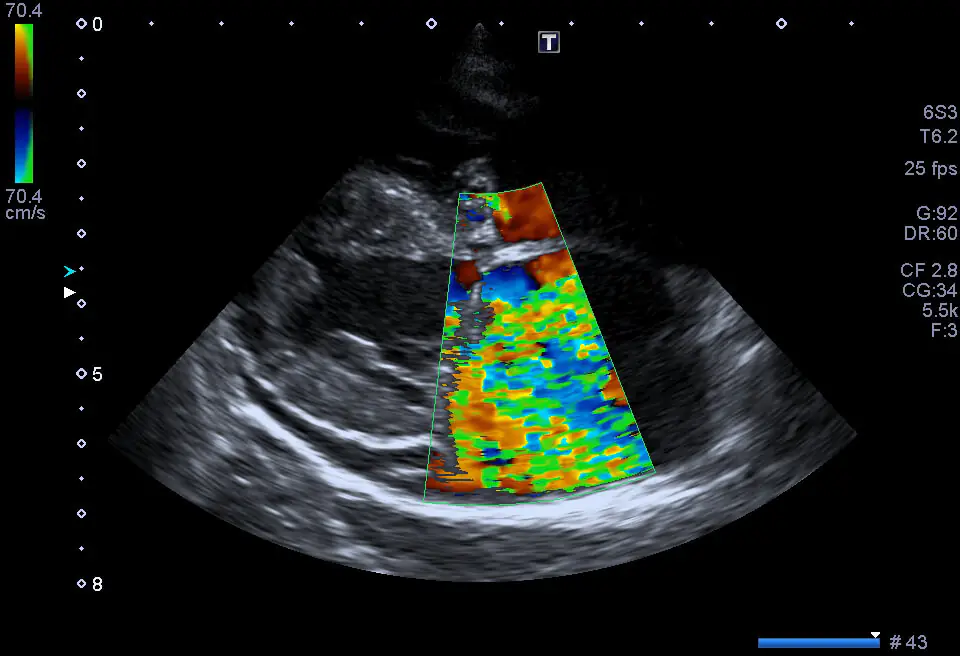

L’Ecocolordoppler cardiaco a riposo, o Ecocardiografia, è un esame non invasivo effettuato da uno specialista in Cardiologia, molto utile nella valutazione delle possibili patologie o malformazioni a carico del cuore. Il medico si serve dell’ausilio di un Ecografo, con sonde apposite, che consente di osservare e capire la forma, la dimensione, il movimento e la conformazione cardiaca.

Se eseguita correttamente, con un buono strumento e da un operatore esperto, essa consente di studiare con grande precisione i flussi interni al cuore, di individuare con esattezza la presenza di una trombosi (blocco di un vaso sanguigno provocato da un ammasso di globuli rossi/piastrine chiamato trombo), di diagnosticare le malattie delle valvole del cuore e di scoprire eventuali difetti congeniti (che cioè sono presenti sin dalla nascita).

Si tratta di un esame diagnostico basato sull’utilizzo di ultrasuoni, totalmente innocuo ed indolore per il paziente. Tramite l’ecografo il Cardiologo può visualizzare le camere cardiache, misurarne le dimensioni, valutare la funzionalità cardiaca e lo stato delle valvole.

Grazie alla funzione di ecocolordoppler cardiaco, si sfrutta l’effetto doppler per studiare la circolazione del sangue nel cuore.